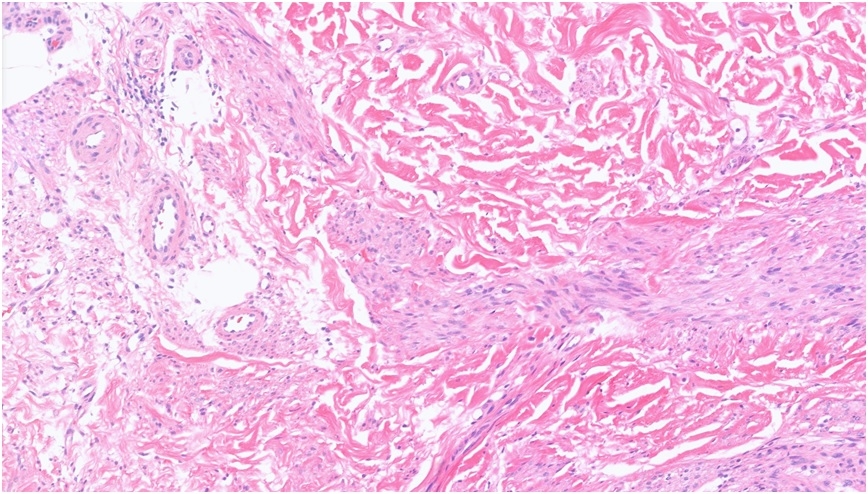

44F, Right shin Excision to exclude DFSP Dermatofibroma (13.10.22) Sudden recurrence of 2x tender lumps on this site; pink, tender 15 mm x 5 mm